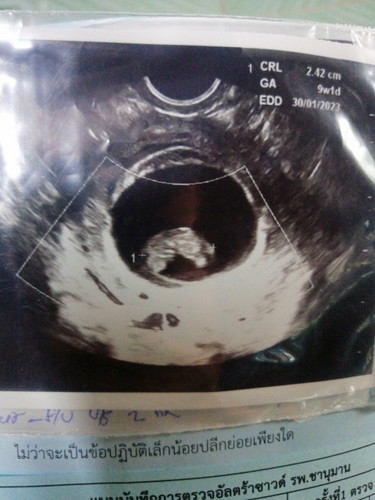

ซาวด์ตอน9วีคพบแค่น้องแต่ไม่พบคลื่นหัวใจ หมอนัดซาวด์อีก2อาทิตย์ ช่วยแชร์ประสบการณ์จะต้องเตรียมใจเตรียมตัวยังไงในท้องถัดไป ท้องแรกด้วยค่ะ การได้พบหน้าเขาครั้งแรกแต่กลับเป็นครั้งสุดท้ายด้วยเช่นกัน... ##ขอบคุณสำหรับคำตอบค่ะ #ขอคำแนะนำหน่อยค่ะ

ของเราตอน9วีคเจอตัวแต่ไม่เจอหัวใจเหมือรกันค่ะ ตอนนี้20วีคแล้วรอดูซาวรอบหน้านะคะ

เจอหัวใจน้องน้อง 11 w คะ ตอน 9w ก็ไม่เจอเหมือนกัน สู้ๆนะคะรออีกนิดเดียว